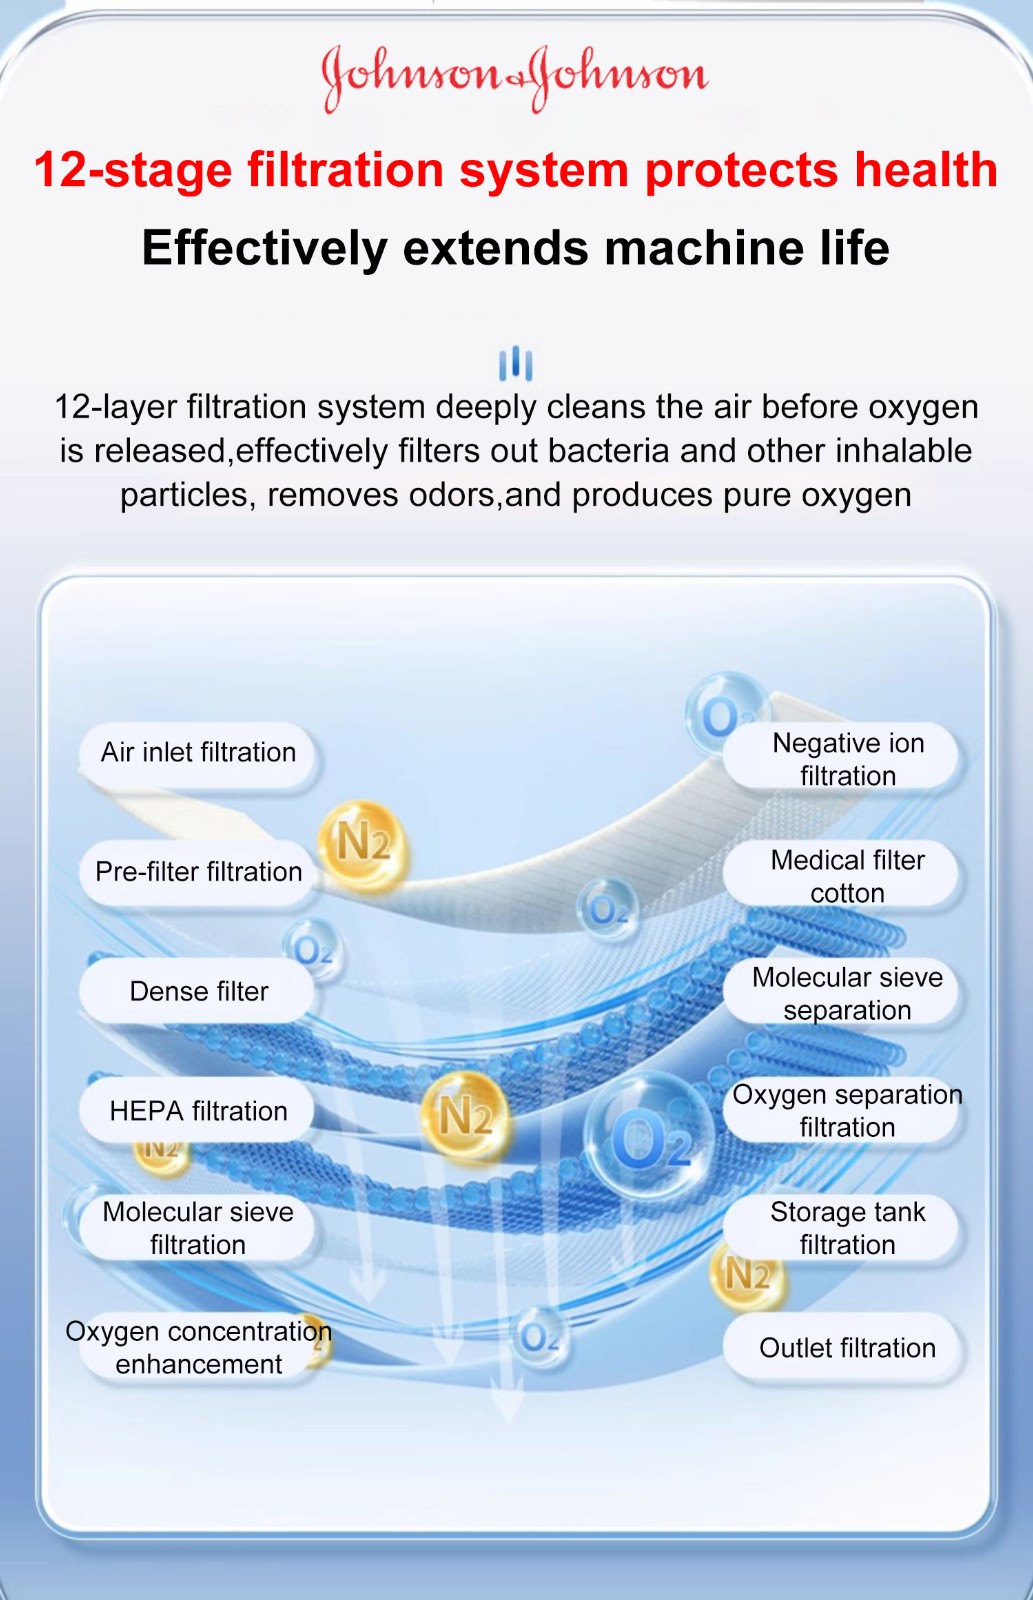

Ο συμπυκνωτής οξυγόνου που πουλάμε είναι ένα προϊόν που αναπτύξαμε μετά από 5 χρόνια έρευνας και ανάπτυξης. Μετά την κυκλοφορία του, έλαβε ομόφωνους επαίνους από αμέτρητους αναπνευστικούς ασθενείς και πουλήθηκε σε εκατοντάδες χώρες σε όλο τον κόσμο.